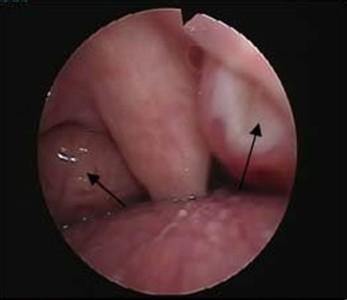

扁桃体炎的症状一般为扁桃体充血、肿胀、化脓。扁桃体的陷窝上出现许多小脓栓,严重的会布满脓苔。经常反炎可形成慢性扁桃体炎,由于炎症使扁桃体生肥大,两侧扁桃体几乎碰在一起,像两扇大门堵住了咽部。扁桃体炎的危害还不止这些,它一旦成为病灶,细菌就会在这里繁殖,并产生毒素,随血液进入人体,使人体发生免疫反应,而这种免疫反应是一种异常的过敏状态,可以进一步导致不少重要脏器得病,如急性肾炎、风湿病等,这些并发症的危害远远过扁桃体炎本身的危害。因此一定要尽早发现及时治疗,以免引发不必要的危害。